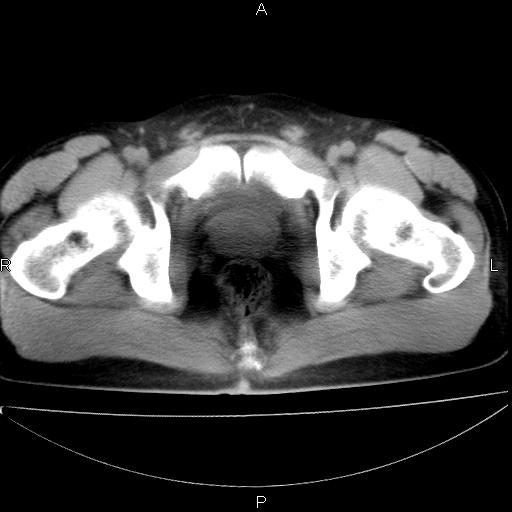

男 25岁 自述 尿频尿急,排尿困难20多天.无腰痛, b超说左肾盂轻度积水,左输尿管上端扩张.未见结石影. ct我看双侧肾盂轻度积水,双输尿管上端都扩张,大家看看能看见结石吗?

双肾轻度积水,双侧输尿管上段扩张(原因待查)。

考虑肾外肾盂 前列腺轻度肿大 密度欠均 考虑炎性改变

箭头所指不是输尿管,壶腹型肾盂。

肾外肾盂,必要时+c